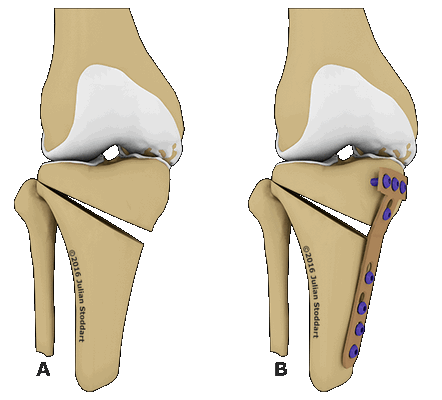

Схематичное изображение проведения операции.

Остеотомия с металлоконструкцией.

Виды хирургических техник

- Клиновидная закрытая. Разрез кожи производится в латеральной или передней области колена для доступа к верхнему эпифизу большеберцовой кости или нижнему эпифизу бедренной кости. После иссечения ткани свободные поверхности кости фиксируют металлическими пластинами или скобами.

- Клиновидная открытая. После разреза кожи в передней или боковой области колена проводится неполная остеотомия. Концевой отдел большеберцовой кости разъединяется на две части с формированием диастаза. Далее костные участки соединяют металлической пластиной и аутотрансплантатом из таза пациента.

Остеотомия коленного сустава: визуальное изображение процедуры.

Костная ткань удаляется с помощью остеотома. Для предотвращения повреждения сосудов и нервов, проходящих через коленный сустав, коррекция проводится под контролем флуороскопа или рентгеновского аппарата. После пластики кожный покров сшивается, и нижняя конечность фиксируется гипсовой повязкой или шиной.

Не существует единого метода оперативного вмешательства, подходящего при любых показаниях. При выборе хирургической техники врач учитывает запланированный угол коррекции. Методы визуализации помогают точнее восстанавливать ось нижней конечности. В современной ортопедии чаще всего проводится открытая клиновидная остеотомия большеберцовой кости выше уровня бугристости.